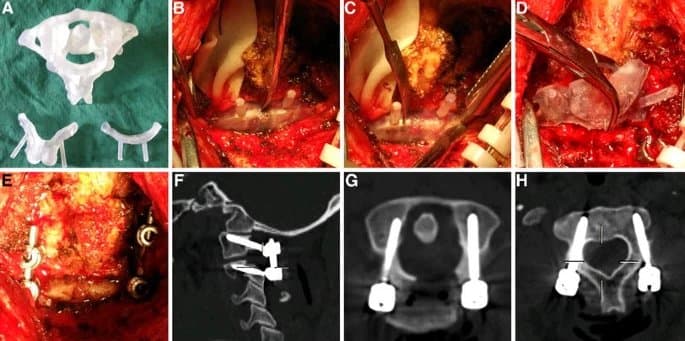

Intraoperative use of drill guides. Intraoperative images revealing placement of the 3D-printed spinal screw trajectory guide placed on the back of the C2 vertebra for case 1 (A) and 2 (C). The occipital plate and C1 laminectomy had already been performed. Final image after insertion of the laminar screws and connection to the occipital plate through rods bilaterally (B and D).

“We describe two patients (three and six years old) requiring occipitocervical instrumented fixation for cervical myelopathy secondary to Morquio syndrome with 3D-SSTGs. In the second case, bilateral laminar screw trajectories were also incorporated into the same guide due to the presence of high-riding vertebral arteries. Registration of the postoperative CT to the pre-operative imaging revealed that screws were optimally placed and accurately followed the predefined trajectory. Both patients had an uneventful recovery from surgery and were discharged from hospital on postoperative day 4. At 5 months following surgery, neither patient developed any infection or wound related complication.”